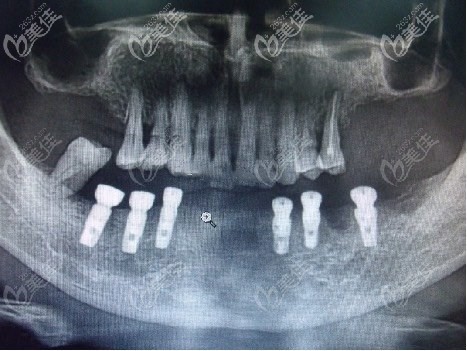

来看看泉州维乐高难度全口牙齿种植效果吧!

种植前陈玉的口腔ct片

老人牙齿ct情况